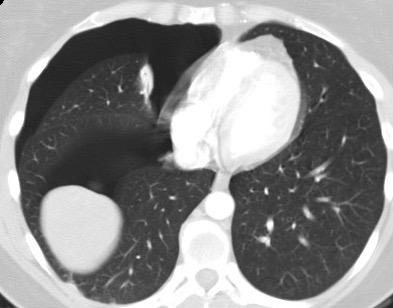

Tromboembolismo pulmonar.

Frecuencia del derrame:

Rx: 32%. TC: 47%

Unilateral. 85%

< 1/3 del hemitórax: 90%

Todos exudados

58% con eritrocitos

21% tabicación lo que causa demora en el diagnóstico

TEP. Empiema pleural. Atelectasia redonda

Porcel JM et al. Analysis of pleural effusions in acute pulmonary embolism: radiological and pleural fluid data from 230 patients. Respirology 2007/ Iguchi T et al. Desquamation of the subpleural lung parenchyma caused by empyema after pulmonary embolism: A case report. Respirol Case Rep. 2022 .